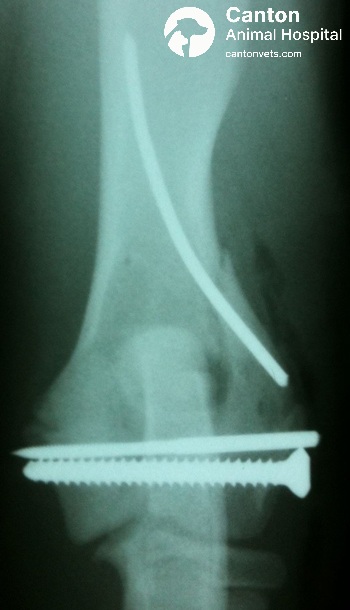

Open reduction and internal fixation (ORIF): Gold standard for treating lateral condylar fractures.

The drill hole is tapped, and the lateral condylar fragment is over-drilled to create a gliding hole before placing a transcondylar lag screw.

After reducing the fracture, the medial condyle is drilled and tapped, and the lag screw is secured across the condyle.

To provide rotational stability, an anti-rotational Kirschner wire is driven from the lateral condyle and seated into the medial cortex of the distal humeral shaft.

The elbow joint is put through a full range of motion to confirm stability and ensure no crepitus is present.